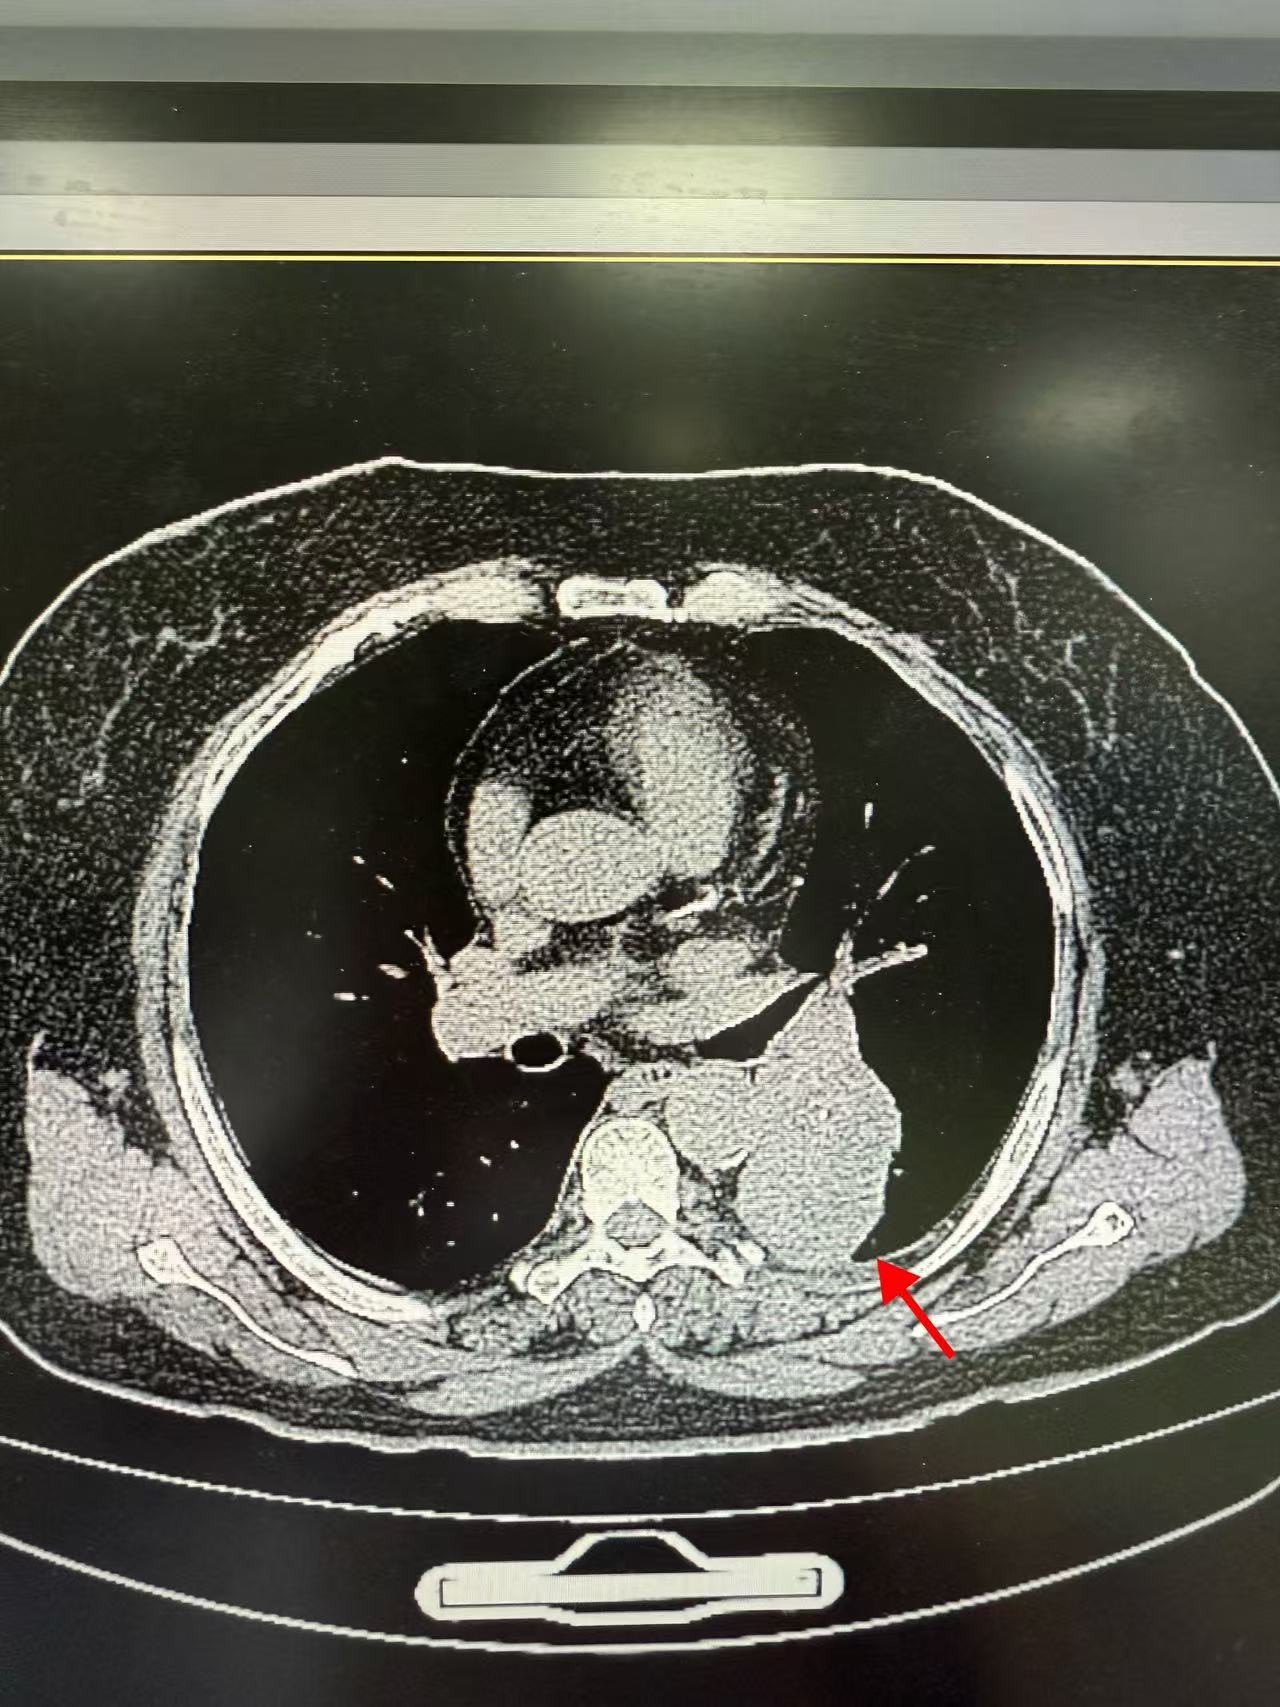

65岁的方女士在常规体检中发现左肺下叶存在一个直径约61×49mm的巨大占位性病变,且位置紧邻肺门,结构关键。

虽然穿刺活检病理初步提示为“较成熟软骨组织及纤维组织,未见恶性肿瘤成分”,由于病灶体积巨大、位置特殊,且穿刺取材范围有限,临床上仍无法完全排除潜在恶性可能。

手术如期进行,周足力教授在胸腔镜探查中,凭借其敏锐的洞察力,发现胸腔内无胸水及胸膜转移,病灶位于左肺下叶背段,突出肺表面,并伴有部分钙化,结合其丰富的临床经验,他高度怀疑为良性错构瘤,术中快速冰冻病理检查结果也证实了其判断——良性病变。